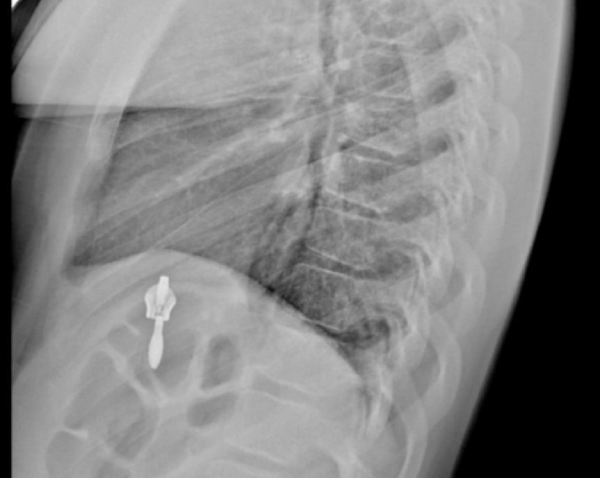

В детскую больницу в Иркутске за сутки поступили пятеро детей с переломами позвоночника

Сразу пять детей с компрессионными переломами позвоночника обратились за сутки в травмпункт Ивано-Матренинской детской клинической больницы в Иркутске. Четверых из них госпитализировали, сообщили в больнице.

- Хотелось бы сказать, что всему виной гололед, но погодные условия стали причиной получения травмы только у одного пациента. Два ребёнка получили компрессионные переломы позвоночника во время прыжков на батутах в развлекательных центрах, один – на тренировке, еще один – во время спортивных соревнований, - рассказали в детской больнице.